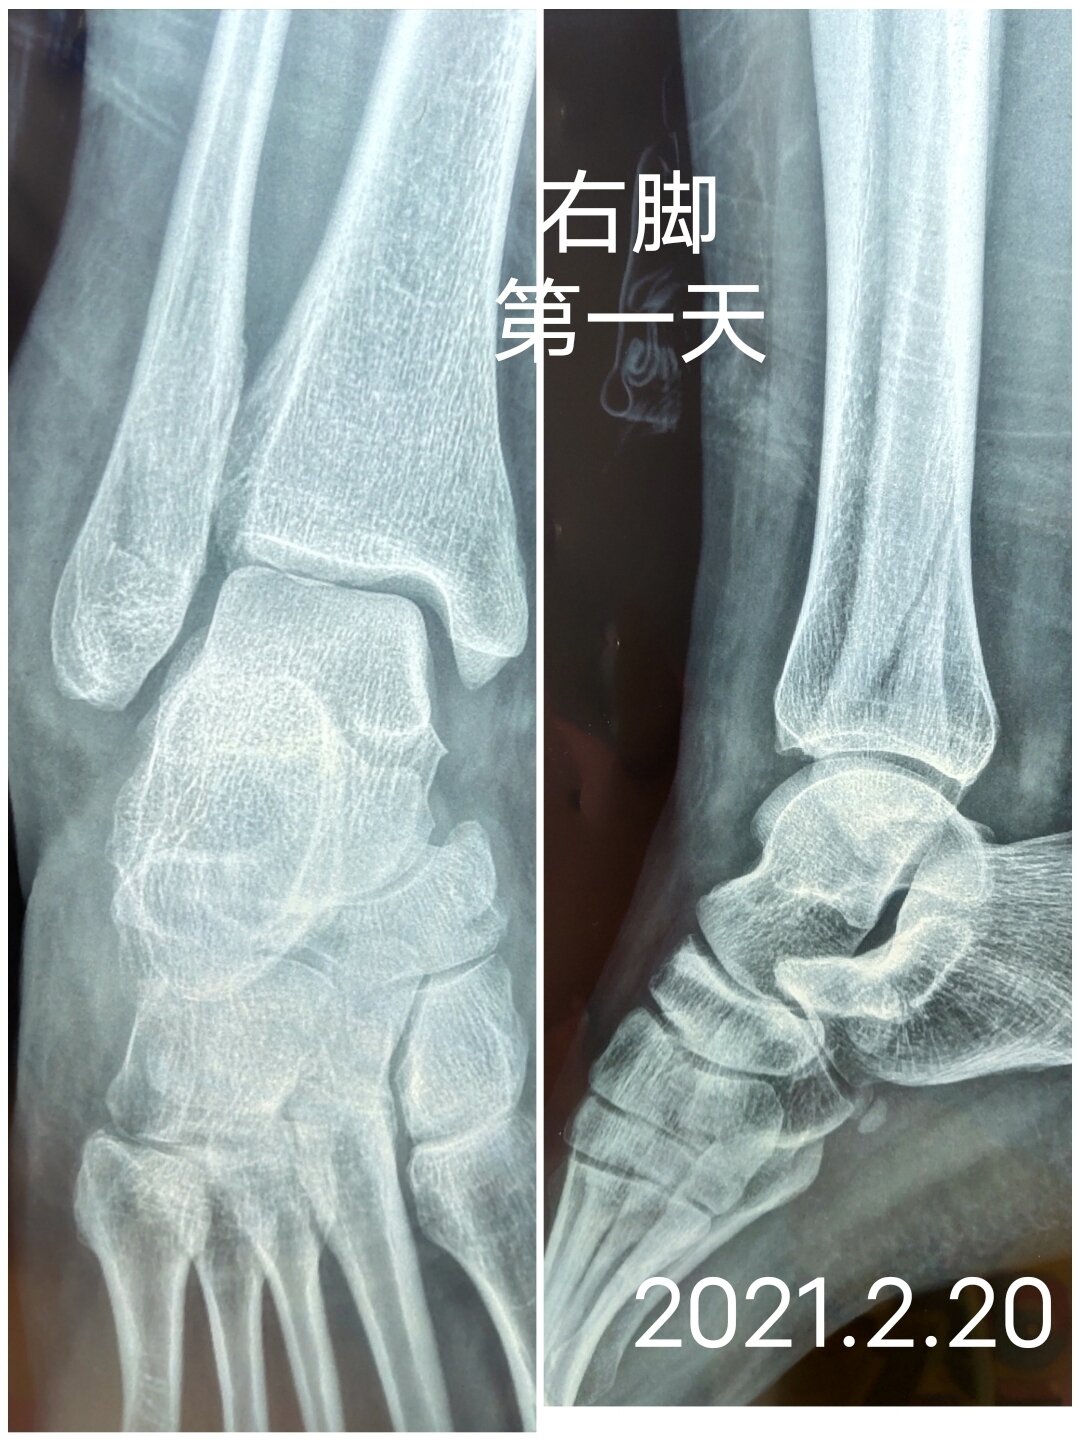

不过勒韦尔自己透漏,场上场下感到不适其实已经有一段时间, 就遭遇了右脚开放性骨折重伤上赛季被交易到步行者那会,勒韦。